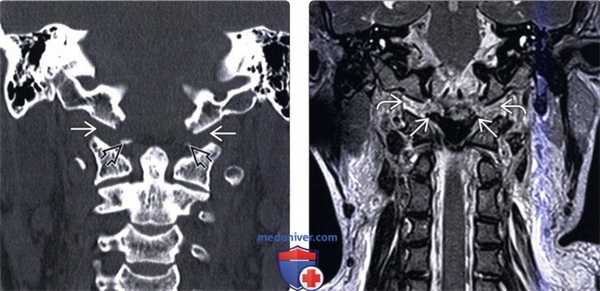

(Слева) КТ, фронтальный срез: расширение суставных щелей атланто-затылочных суставов (АЗС). Небольшие костные фрагменты представляют собой отрывные переломы нижне-медиального края мыщелков затылочной кости. Переломы в области прикрепления связок эквиваленты разрыву этих связок и только усиливают выраженность нестабильности КВС.

(Справа) Т2-ВИ, фронтальная проекция: расширение и гиперинтенсивность сигнала обоих АЗС. Также здесь видно нарушение непрерывности обеих крыловидных связок.